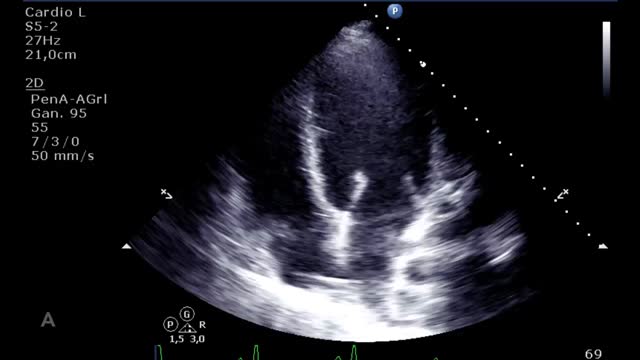

En la evaluación para el implante de una ECMO VV otro factor esencial es la función del ventrículo derecho (VD). Muchos pacientes con síndrome de distrés respiratorio agudo grave presentan hipertensión pulmonar y disfunción del VD en relación con la hipoxia, la hipercapnia, el aumento de la presión de las vías aéreas y la ventilación mecánica. La ECMO VV, al corregir la hipoxia y la hipercapnia, disminuye la poscarga y puede mejorar la función del VD de manera que se corrija la inestabilidad hemodinámica. En caso de presentar una disfunción ventricular derecha significativa será importante realizar un seguimiento ecocardiográfico y, si se perpetúa la situación de shock y no mejoran los parámetros ecocardiográficos a pesar de la ECMO VV, habría que plantear un cambio de estrategia a un VA o veno-arteria-vena. Para la evaluación de la disfunción del VD valoraremos: desplazamiento sistólico del plano del anillo tricuspídeo<16mm, onda S’<10cm/s, fracción de acortamiento<35%, relación área telediastólica VD/VI>0,6 significativa y >1 grave o aplanamiento/abombamiento (en forma de «D») del septo interventricular tanto en sístole como en diástole (suplementario 1). Esta interdependencia se puede cuantificar a través del índice de excentricidad ventricular, que es el cociente entre el diámetro septo-cara inferior y cara anterior-cara inferior en sístole y diástole, siendo su valor normal=118.

Evaluación ecocardiográfica de destete de paciente con ECMO VA. Ecografía transtorácica e integral velocidad-tiempo (IVT) del tracto de salida del ventrículo izquierdo al reducir flujo (A: 3L/min, B: 2,5L/min, C: 2L/min) de ECMO VA. Obsérvese el aumento del tamaño de la IVT y consecuentemente del volumen sistólico y del gasto cardiaco.